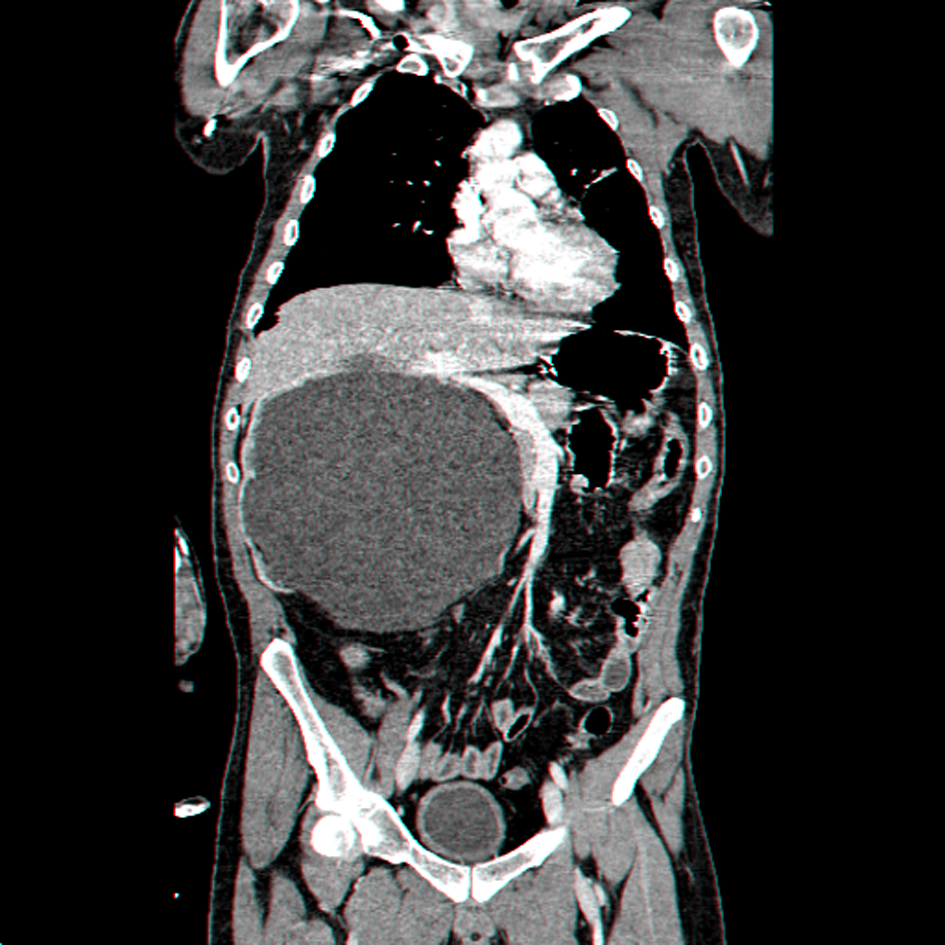

A 27-year-old man, dumb, deaf and with mild mental retardation, presents in the Emergency Room (ER) with sepsis secondary to community-acquired pneumonia. During assessment in the ER was detected a large painless abdominal mass, localized in the right upper quadrant and extending into the pelvis. He had no prior history of colic, urolithiasis, or infection. Computed tomography revealed severe right hydronephrosis and thinning of renal parenchyma (Fig. 1, 2) due to probable congenital UPJ obstruction, with compression of adjacent viscera and lateralization of the great vessels (Fig. 3). The left kidney was normal. Blood analysis presented a normal renal function.

![]() Click for large image | Figure 3. Coronal reconstruction CT scan showing giant right hydronephrosis with pressure effect over the bowels and liver, associated with lateralization of the great vessels. |